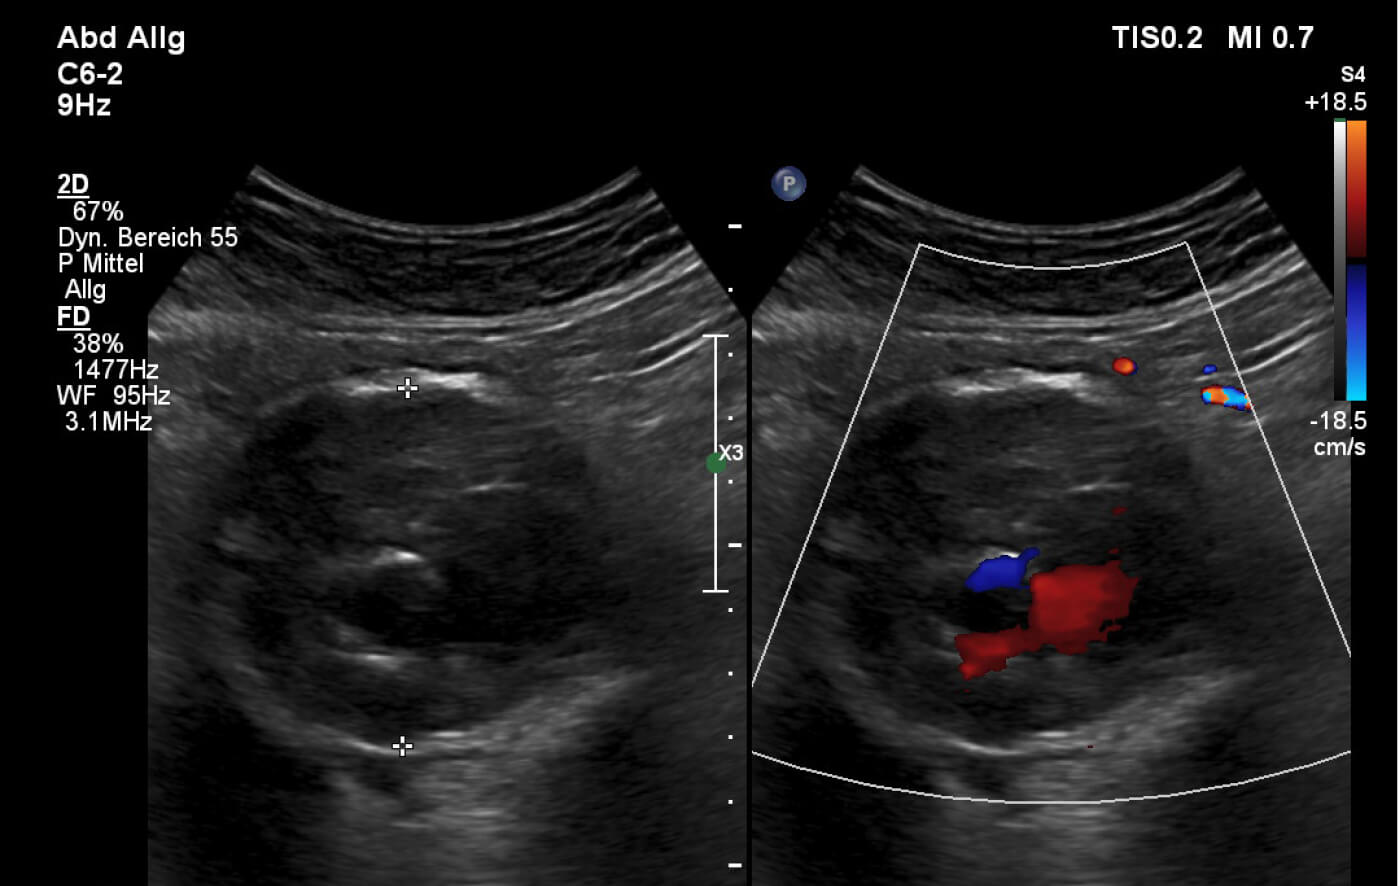

Unsere Praxis bietet das Ultraschall-Screening (Sonographie) der Bauchschlagader an. Die Untersuchung dauert nur wenige Minuten und kann eine Erweiterung der Aorta zuverlässig feststellen.